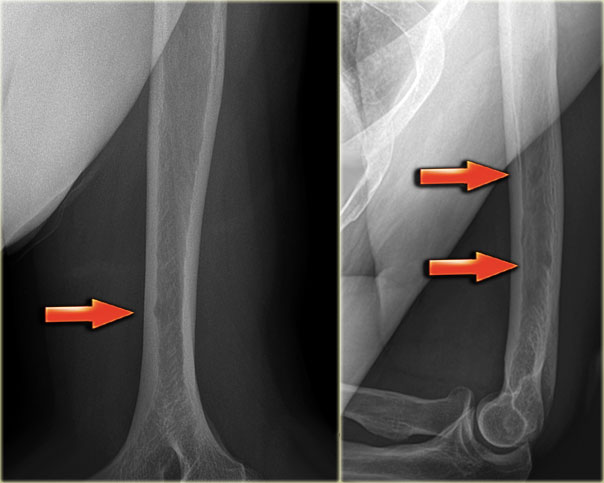

Here a typical osteoid osteoma in the tibia.

X-ray an CT-image of a typical osteoid osteoma in the proximal tibia.

Notice the sclerotic center within the osteolytic lesion (red arrow).

MR-images of the same patient demonstrate cortical thickening and extensive edema.